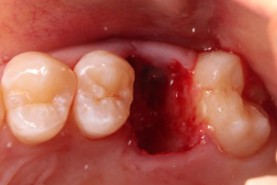

20代 男性

治療前

- 20代/男性

- 患者の具体的な症状

- 1年前に左上12 右上1の根の治療をし、その後放置していたら、左上2が破折した。

左上2インプラント補綴 左上1右上1オールセラミック装着。

歯根破折と虫歯による痛み、審美障害を主訴として来院。 - 検査方法

- コーンビームCT、レントゲン撮影

- 診断結果

- 左上2 歯根破折

- 治療詳細

- 左上抜歯後、インプラント埋入1本

骨造成あり 局所麻酔

インプラント治療後、左上1右上1セラミック修復2本 - 通院回数

- 9回

- 治療期間

- 12か月